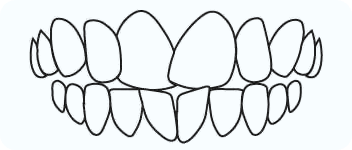

Open Bite

In open bite there is no vertical overlap between teeth and open space exists between upper and lower teeth when jaws are closed.